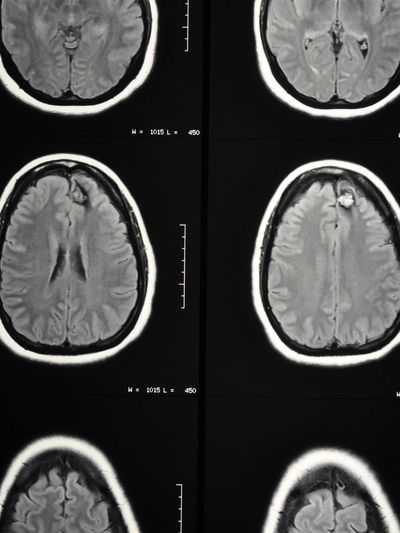

Diagnosing arteriovenous malformation (AVM) typically involves a combination of medical history evaluation, neurological examination, and imaging studies. The process of diagnosis may include the following steps:

Imaging Studies:

Once diagnosed, the medical team will evaluate the size, location, and specific characteristics of the AVM to determine the appropriate course of action. Treatment options may include observation for asymptomatic AVMs, surgery, endovascular embolization (blocking the abnormal vessels), stereotactic radiosurgery (focused radiation therapy), or a combination of these approaches.